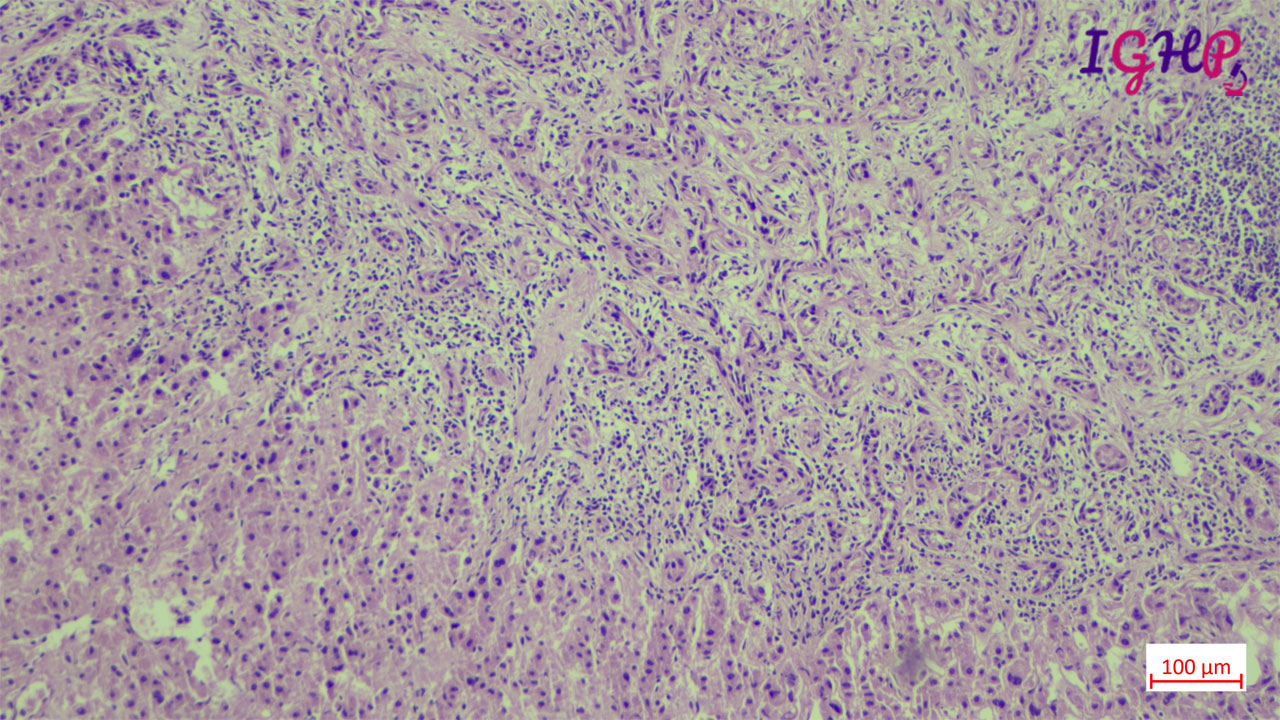

Microscopic examination showed an unencapsulated proliferation of uniformly spaced ductules lined by bland, cuboidal epithelium in a collagenous stroma. The architecture seems non-infiltrative, with evidence of entrapped native portal tracts present within the lesion itself.

BDA is an important diagnosis in frozen section examination. This needs to be differentiated from malignant nodules. Peripheral subcapsular location, presence of portal tracts within the lesion, inflammatory infiltrate and mild atypia favours a bile duct adenoma. Immunohistochemistrywith lowKi67 and wild type p53 may be used as adjunct.